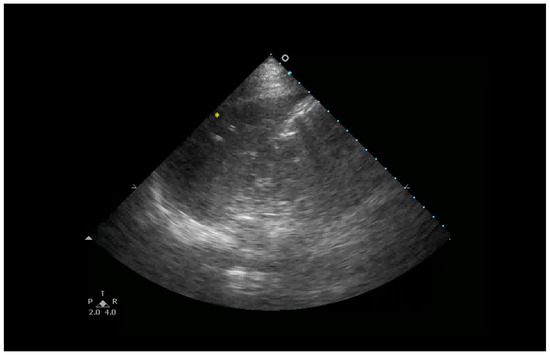

- Anterior subpleural consolidations;

- Absent or reduced lung sliding;

- “Preserved areas” of normal lung parenchyma;

- Abnormalities in the pleural line (e.g., fragmented, thickened, or irregular pleural line);

- Inhomogeneous distribution of B-lines.